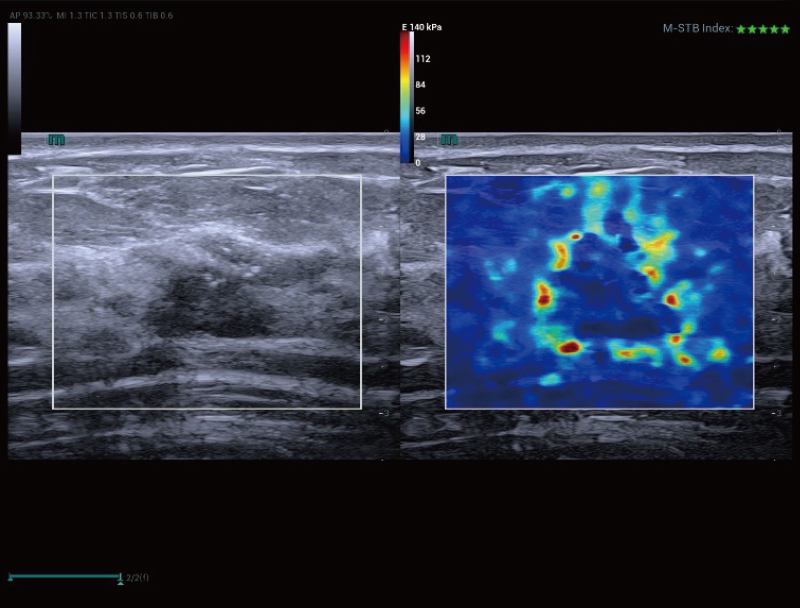

STVi maakt de kwantitatieve evaluatie van weefselviscositeit mogelijk en biedt realtime, multi-parametrische beeldvorming. Dit maakt een bredere benadering mogelijk van beeldvormingsdiagnose en kwantitatieve analyse van chronische leverziekten, borstlaesies en andere aandoeningen.

Beoordeling van borsttumoren